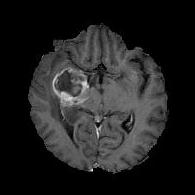

We argue that the sub-optimal paradigm of processing different abstractions within a single CNN pipeline can be remedied through the effective processing of information in a structured manner. Consequently, we devise strategies for disentangling the edge and texture information within a single training pipeline. Figure 2 illustrates how our proposed module, dubbed EG-CNN, can be paired with any existing CNN encoder-decoder to improve segmentation quality near intensity edges. We have applied our EG-CNN to the tasks of brain and liver tumor segmentation in medical images (Figure 3).

(1) Brain MR (2) Liver MR (3) Liver CT (4) Lung CT

Deep Active Lesion Segmentation

[45]: Lesion segmentation is an important problem in computer-assisted diagnosis that remains challenging due to the prevalence of low contrast, irregular boundaries that are unamenable to shape priors. We introduce Deep Active Lesion Segmentation (DALS), a fully automated segmentation framework that leverages the powerful nonlinear feature extraction abilities of FCNs and the precise boundary delineation abilities of ACMs. Our DALS framework benefits from an improved level-set ACM formulation with a per-pixel-parameterized energy functional and a novel multiscale encoder-decoder CNN that learns an initialization probability map along with parameter maps for the ACM. We evaluate our lesion segmentation model on a new Multiorgan Lesion Segmentation (MLS) dataset that contains images of various organs, including brain, liver, and lung, across different imaging modalities—MR and CT. Our results demonstrate favorable performance compared to competing methods, especially for small training datasets. -